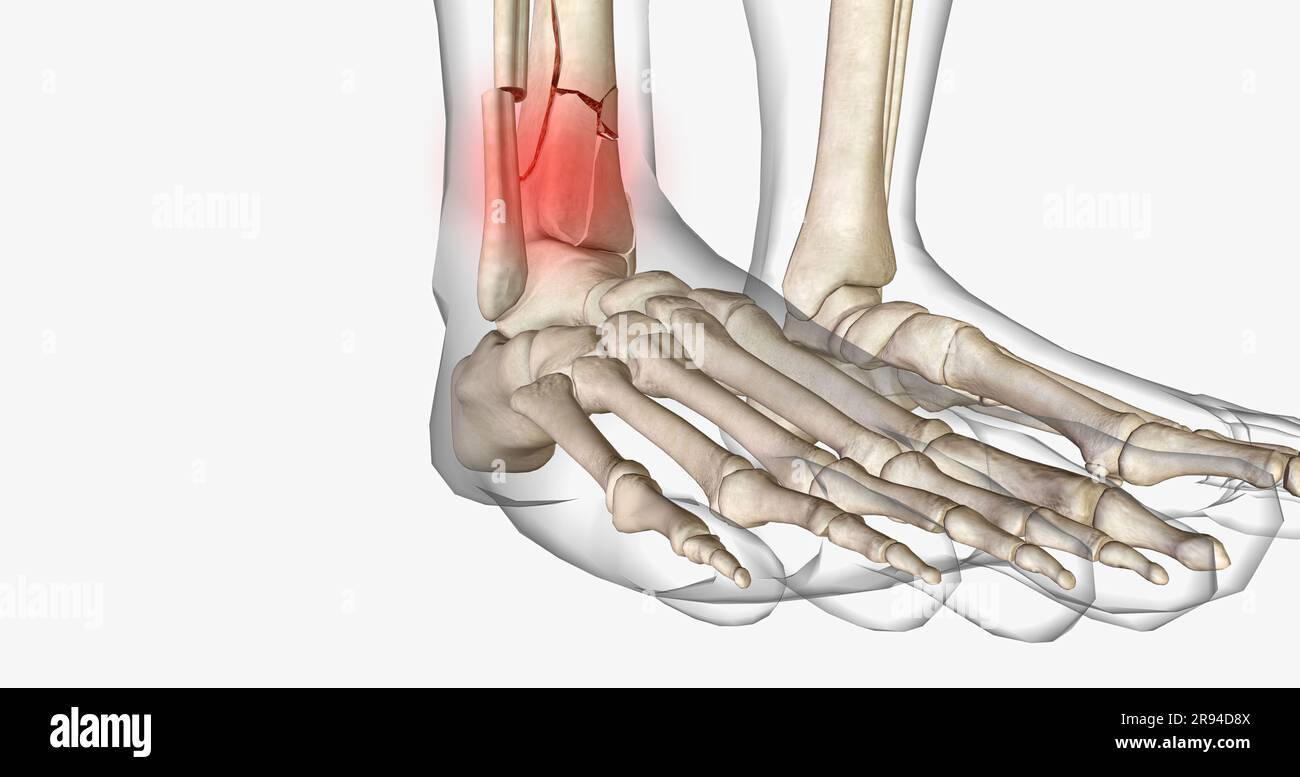

Fracture Du Péroné Sans Plâtre. Fracture de la partie inférieure du péroné, sagittale vue Xray Photo Stock Alamy L'avantage du plâtre est qu'il va quand même parfaitement immobiliser la fracture Si la fracture concerne la diaphyse du péroné, le plâtre devra englober également la moitié de la cuisse

Fracture de la partie inférieure du péroné, sagittale vue Xray Photo Stock Alamy. Quels sont les symptômes de la fracture du péroné ? La durée de récupération après une fracture non déplacée peut varier en fonction de plusieurs facteurs, tels que la gravité de la blessure, l'emplacement de la fracture et le traitement reçu